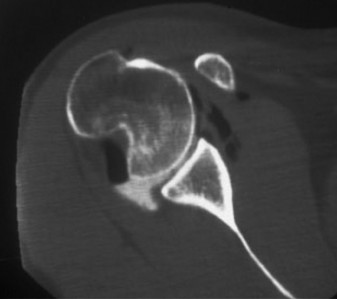

The answer is (B). As the four layers of the lateral rotator interval insert onto the lesser tuberosity of the humerus, they form the “reflection pulley” that forms a sling around the tendon of the long head of the biceps before it enters the bicipital (intertubercular) groove. A tear of the upper part of the subscapularis can disrupt this reflection pulley and destabilize the biceps tendon, allowing it to sublux or even

dislocate out of its groove, usually in a medial direction. If this happens, the intertubercular groove will be empty on MRI. Often, a “pulley sign” will also be seen on MRI when this occurs. This is when contrast material extravasates extra-articularly just over the superior border of the subscapularis tendon on axial images (see Fig. 2–11).

Figure 2–11_Axial T1 MRI. Left: an empty intertubercular sulcus, positive pulley sign (straight _black arrow on left), and dislocated biceps tendon (curved black arrow). Right: fraying subscapularis tendon (arrow). (From Lyons RP, Green A. Subscapularis tendon tears. J Am Acad Orthop Surg. 2005;13(5):353–363.)

A high riding humeral head on plain films (Answer A) is associated with a massive rotator cuff tear and is the first sign of progression to cuff tear arthropathy that is seen on plain film.